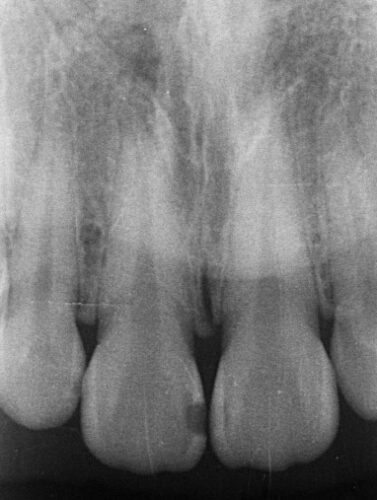

根の先が黒くなっています。

これは、膿がある状態です。

根っこの先まで器具を通し、洗浄して、お薬で密封する必要があります。

しっかりと根っこの先まで薬剤が入っている事が確認できます。